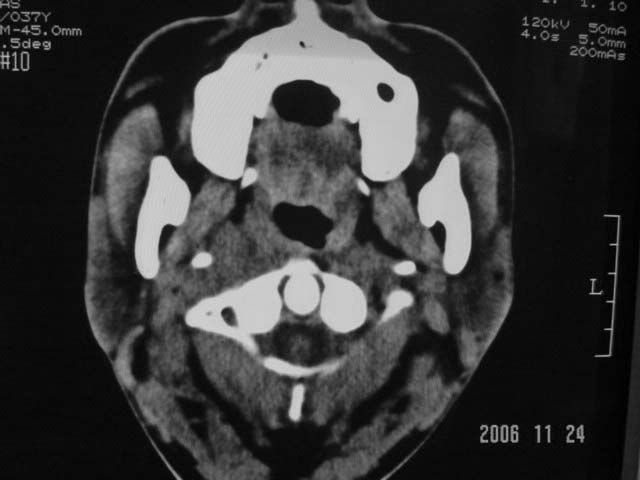

标题: CT5388:鼻塞、耳鸣3个月,涕中带血2周,颈部可触及肿大淋 [打印本页]

右侧鼻咽部软组织肿块,颅底骨质破坏,右侧颈部淋巴结肿大;诊断:鼻咽ca、右颈部淋巴结转移、颅底侵犯

右侧鼻口咽侧后壁不规则增厚,内可见密度不均匀性椭圆形软组织块影,边界欠清,咽旁间隙尚清.右颈部可见圆形软组织块影,鼻塞、耳鸣3个月,涕中带血2周,颈部可触及肿大淋巴结,考虑鼻咽癌,颈部淋巴转移.

右侧鼻咽后壁不规则增厚,内可见密度不均匀性椭圆形软组织块影,边界欠清,咽旁间隙尚清.右侧下方可见圆形软组织块影,双侧蝶窦呈均一高密度。

考虑:1、右侧鼻咽癌伴颈部淋巴结转移;

2、双侧蝶窦炎。

右侧鼻咽部软组织肿块,颅底骨质破坏,右侧颈部淋巴结肿大;诊断:右侧鼻咽ca伴右颈部淋巴结转移、颅底侵犯.

典型右侧鼻咽ca伴颈部淋巴结转移,中颅底骨侵蚀。

右侧鼻咽侧后壁不规则增厚,咽隐窝变钝,咽旁间隙变狭窄,见组织结节影[哨兵征],蝶骨似破坏,蝶窦内充塞软组织影,翼内外肌上分间隙模糊,右颈后三角区淋巴结肿大,右侧乳突增高气房消失。考虑鼻咽癌伴蝶窦侵犯及淋巴结转移,右侧浆液性中耳炎。其他恶性病变待排。